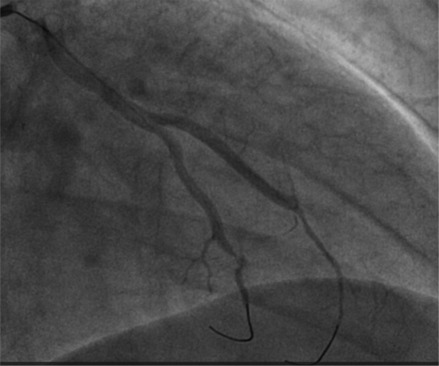

We present a case of a 48-year-old man with an atypical type 2 myocardial infarction (MI)/myocardial infarction with nonobstructive coronary arteries, caused by a coronary embolism originating from the inferior vena cava and passing through a patent foramen ovale (PFO). The patient presented to the emergency department with oppressive retrosternal chest pain. His medical history included papillary renal cell carcinoma and seminoma with recent abdominal lymph node recurrence. The electrocardiogram indicated an inferolateral ST-segment elevation (STE), prompting emergency coronary angiography, that revealed distal occlusion of the circumflex artery and the obtuse marginal branch, suggesting an embolic etiology. Stent placement was deferred, and the management approach involved thromboaspiration and unfractionated heparin infusion. Abdominal imaging identified a thrombotic formation in the inferior vena cava and a transesophageal echocardiogram revealed a PFO with a right-to-left shunt, supporting the diagnosis of a paradoxical embolism. Follow-up coronary angiography showed vessel patency, and the patient was then treated with low-molecular-weight heparin. This case underscores the importance of considering alternative etiologies for STE myocardial infarction beyond acute plaque rupture, highlighting the need for individualized management strategies, particularly in patients with complex medical histories, and given the lack of standardized treatment guidelines for coronary embolism.